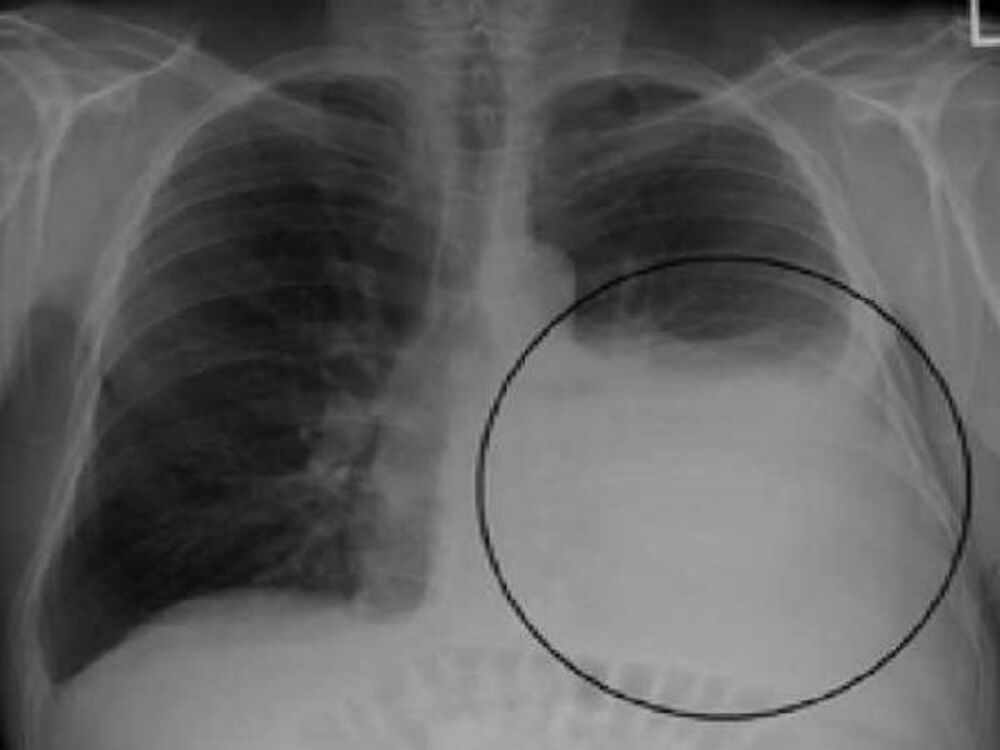

Skrining program podrazumeva detekciju karcinoma pluća pomoću niskodoznog skenera (LDCT), uz pomoć kojeg se se mogu prikazati manje tumorske senke, koje nije moguće videti uobičajenim dijagnostičkim postupcima (RTG).

Ovom metodom do sada je pregledano više od 1.200 pacijenata, a kod više od 30 otkriven je karcinom pluća koji je bio asimptomatski i najveći broj u početnom stadijumu, navodi se u saopštenju.